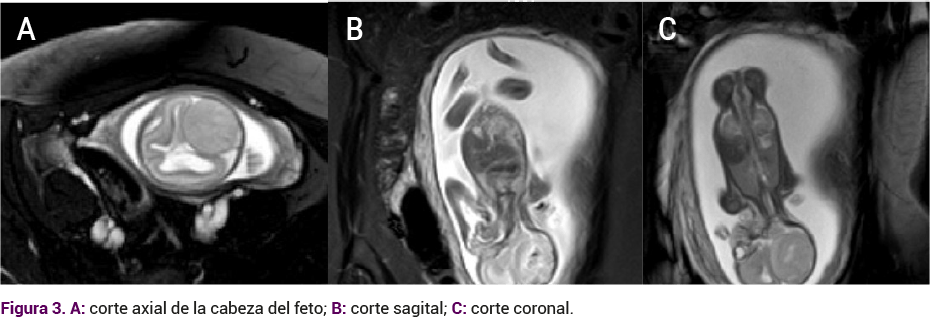

Un mes después se solicitó una resonancia magnética fetal (Figura 3) en la que se reportó al sistema nervioso central con dilatación del sistema ventricular supratentorial hacia el asta occipital izquierda de 11 mm, asta derecha de 9 mm, tercer ventrículo de 7 mm, medidas promedio de 3 mm de las astas frontales. Además, se evidenció una lesión ocupante del espacio extra axial occipital izquierdo, con imagen de ausencia de señal central. Esa lesión era heterogénea, de 33 x 28 x 22 mm, con rechazo secundario de las astas occipitales, cuerpo calloso y cisternas de base normal. La impresión diagnóstica fue de lesión extra axial occipital sugerente de meningioma comparada con un hemangiopericitoma.

<strong>Figura 3</strong>

Figura 3.